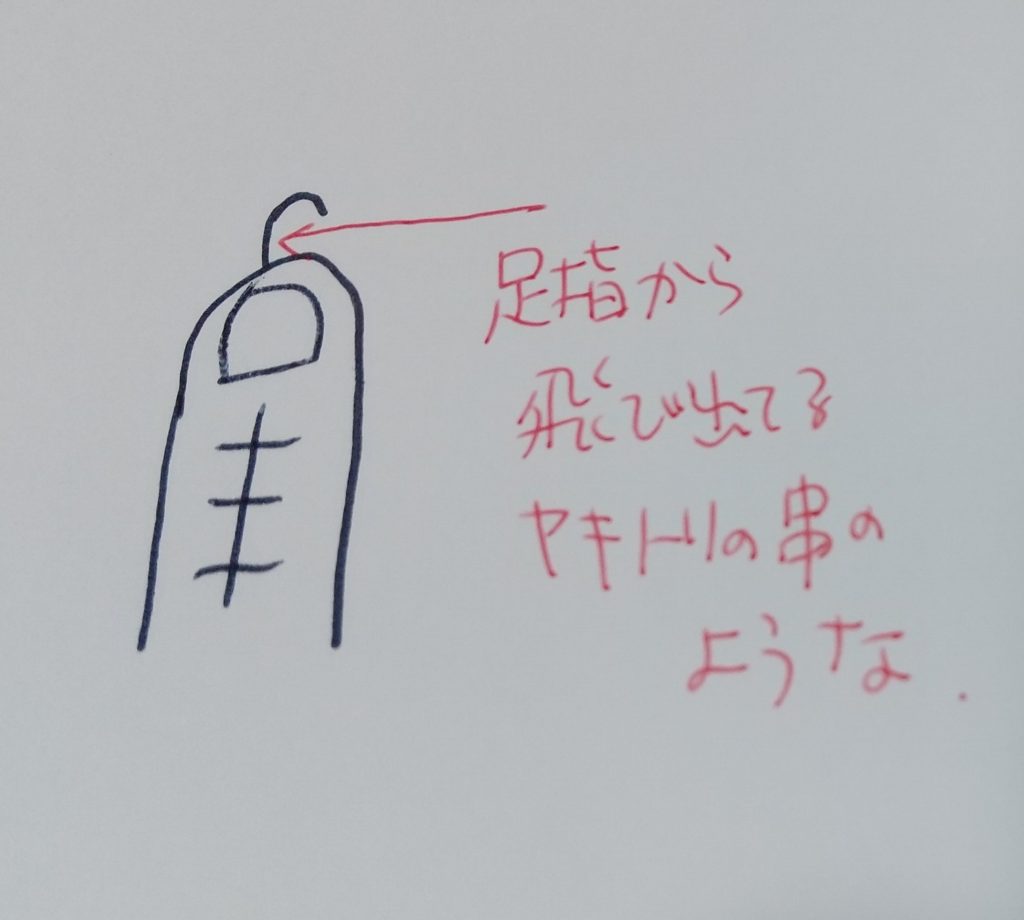

女性医師ではきはきしていらしてとても好感がもてました。(基本的に医師に対しての性差はあまり感じない派)説明も自分なりに納得がいきました。日帰り手術で、麻酔をして、まず、経皮的固定ができればそれで終わり。できなければ、観血的整復固定、つまり、切りますよ、という。そのうえで、骨の位置を正して、焼き鳥の串のようなものを指しますとのことでした。

「焼き鳥?」とおもいましたが、その段階ではどういう状況だか想像できず笑。ただ、そこは食い下がるところではないので、聞き流しました。手術時間は1時間くらいだろうとのこと。

包帯の中身は怖くて外してまでは確認できませんでしたが、後日消毒の時に写真を撮ってみました。さすがにその写真はのっけられないので、絵に描いてみたらこんな感じ。

足指の甲の部分に切った傷があり、爪の上、足指の先から本当に金属棒がびよーんて飛び出ていました。それを金属板(アルフェンスと診療明細には書いてありました)でカバーして、それをテープで固定。からの包帯ぐるぐるという感じです。傷を見て「なるほど、確かにこれは焼き鳥やバーベキュー風だ」と思った次第です。